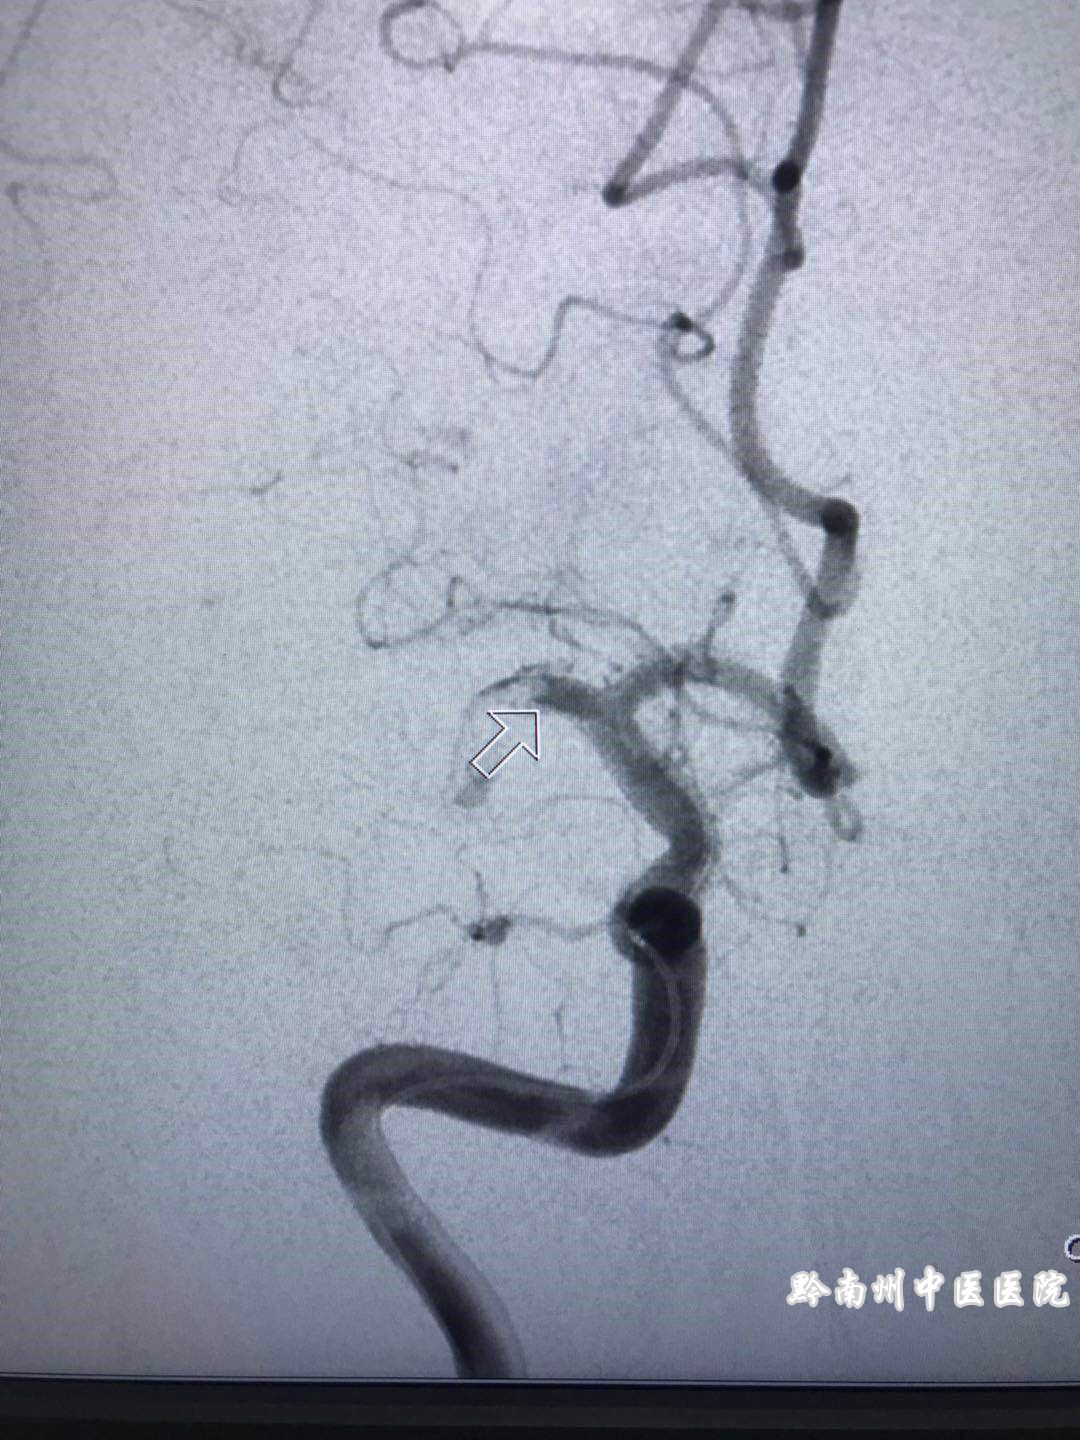

(造影见右侧大脑中动脉M1段主干闭塞(箭头所指),与临床症状及头颅CT吻合。)

0时30分:导管到达闭塞处、使用尿激酶40万单位溶栓,溶栓后造影见闭塞未通